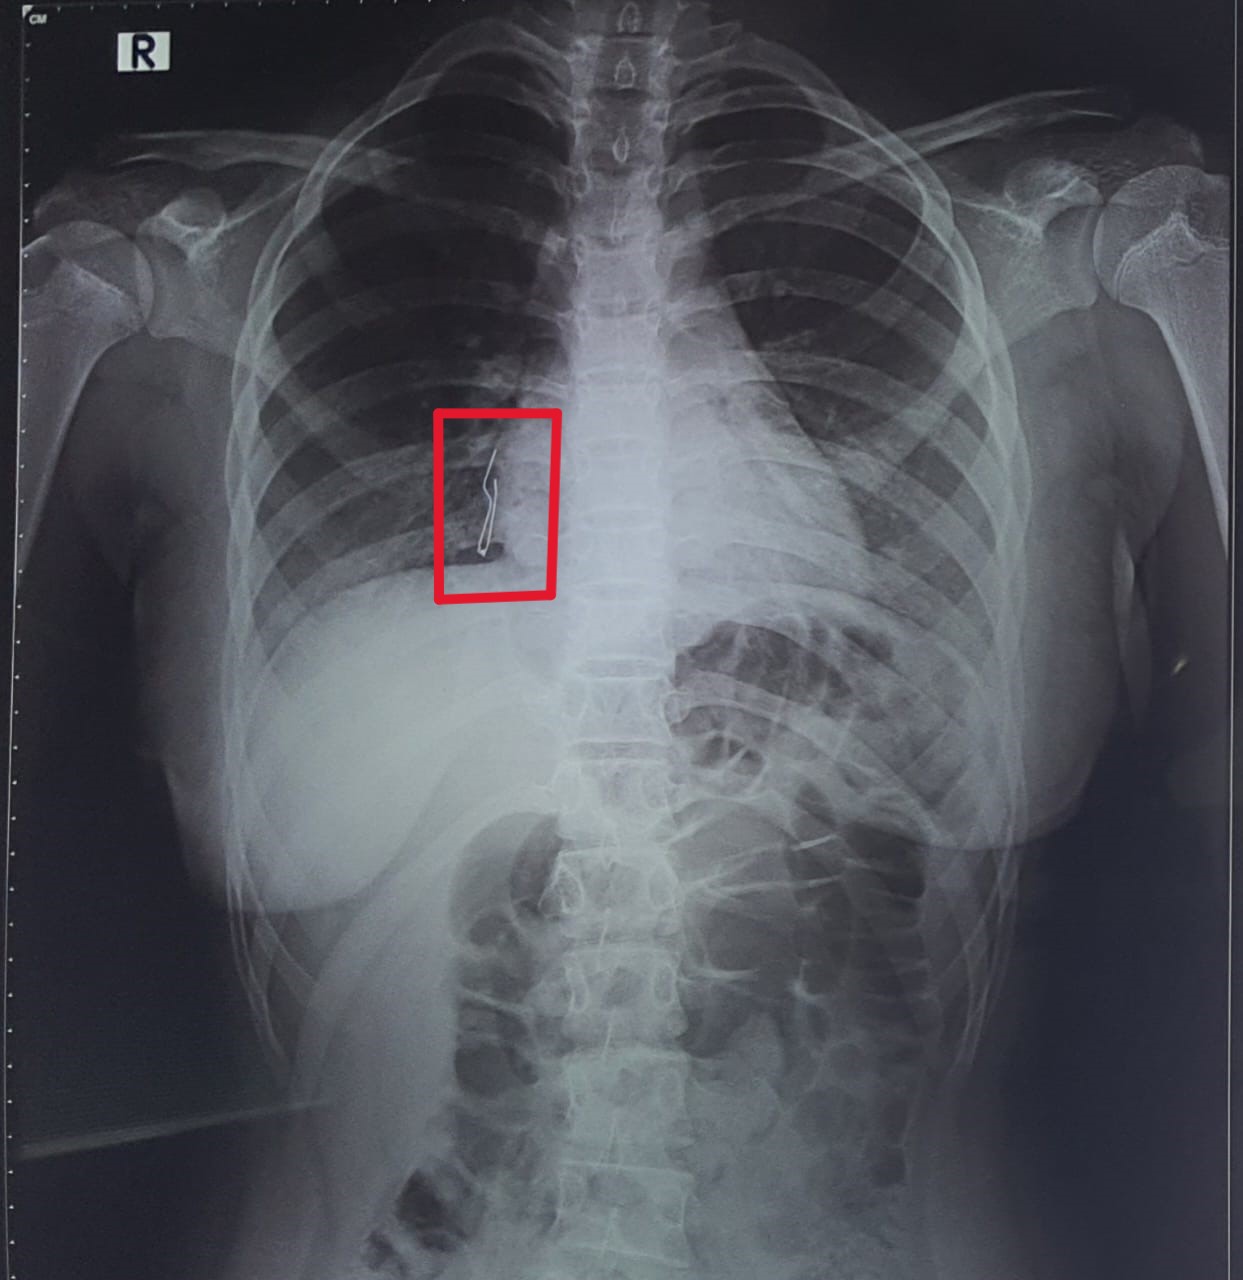

According to a release, the girl presented to the emergency room with a foreign object (LED light) stuck in the bronchus. She was initially taken to a private hospital, where doctors tried to remove the object, but could not retrieve it. At the KKCTH, an X-ray showed that the object was stuck in the right terminal bronchus.